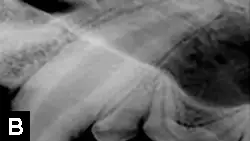

• When a young patient (<12 months of age) acutely fractures a tooth, time is of the essence. At this age, the permanent teeth are usually not fully formed; the walls of the tooth are very thin, and the apex of the root is not closed (Figure 4).

• If untreated, any fracture or trauma can cause an immature tooth to become nonvital; if nonvital, these teeth should be extracted because of lack of function or predisposition to further fractures.

• To preserve immature teeth, treatment by vital pulp therapy (Figure 5) should be pursued within 48 hours of the tooth fracture.3,4